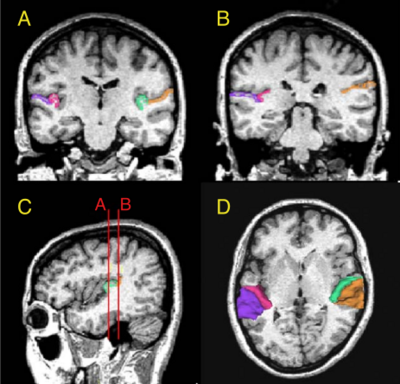

Fig. 1. (Panels A and B) Delineation of Heschl’s gyrus and planum temporale in a coronal slice in rostral and caudal part of regions of interest, respectively, based on MRI data of a control subject. The gray matter of Heschl’s gyrus is labeled green on subject left and wine-red on subject right. The gray matter of planum temporale is orange on subject left and violet on subject right. (C) Sagittal view of the Heschl’s gyrus and planum temporale in the left hemisphere. The coronal lines A and B correspond to the planes of panels A and B, respectively. (D) Three-dimensional reconstruction of Heschl’s gyrus and planum temporale gray matter superimposed on the axial plane. Each region is labeled using the same color as that in panels A, B and C.

Publication: NeuroImage 2004; 22:720–727. PDF

Background/Purpose: Schizophrenia is associated with language-related dysfunction. A previous study [Schizophr. Res. 59 (2003c) 159] has shown that this abnormality is present at the level of automatic discrimination of change in speech sounds, as revealed by magnetoencephalographic recording of auditory mismatch field in response to across-category change in vowels. Here, we investigated the neuroanatomical substrate for this physiological abnormality. Thirteen patients with schizophrenia and 19 matched control subjects were examined using magnetoencephalography (MEG) and high-resolution magnetic resonance imaging (MRI) to evaluate both mismatch field strengths in response to change between vowel /a/ and /o/, and gray matter volumes of Heschl's gyrus (HG) and planum temporale (PT). The magnetic global field power of mismatch response to change in phonemes showed a bilateral reduction in patients with schizophrenia. The gray matter volume of left planum temporale, but not right planum temporale or bilateral Heschl's gyrus, was significantly smaller in patients with schizophrenia compared with that in control subjects. Furthermore, the phonetic mismatch strength in the left hemisphere was significantly correlated with left planum temporale gray matter volume in patients with schizophrenia only. These results suggest that structural abnormalities of the planum temporale may underlie the functional abnormalities of fundamental language-related processing in schizophrenia.